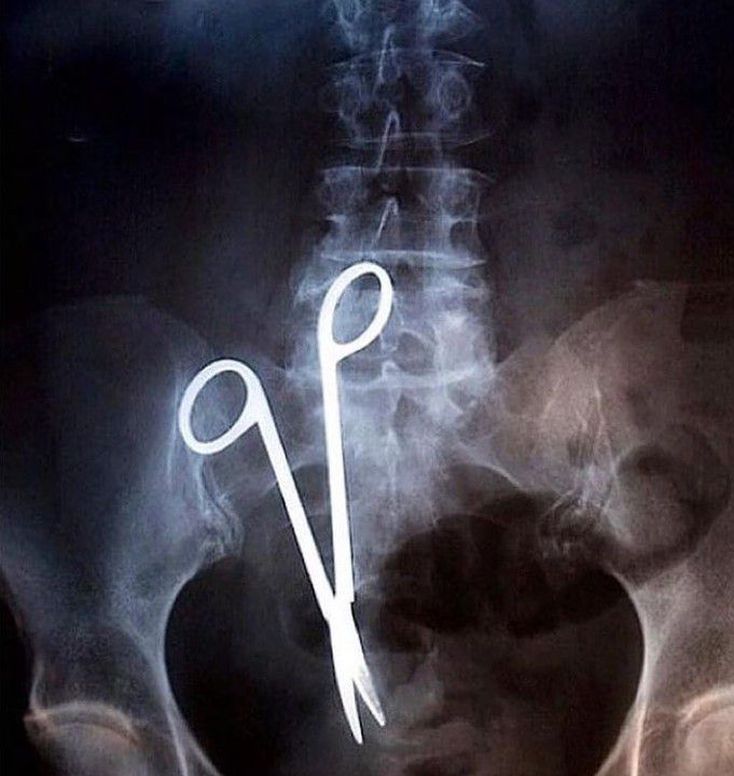

A middle aged woman who had an abdominal surgery 18 months ago kept complaining about the persistent abdominal pain.A pair of 6.7 inch long surgical scissors were found in the X-ray. Image via : https://www.instagram.com/p/CJgACUXHE7-/?igshid=1c8ku6ahlw2xi